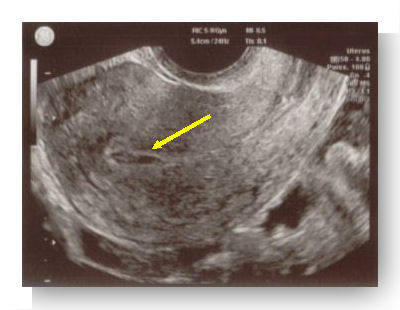

Échographie pelvienne

L’échographie pelvienne retrouve le plus souvent des signes indirects de grossesse extra-utérine :

- Vacuité utérine (l’utérus est vide) ou présence d’un pseudo sac gestationnel (image construite par le sang présent dans l’utérus) ;

- Hématosalpinx (présence d’une collection sanguine dans une trompe utérine. Ce signe échographique est présent dans 80 % des GEU) ;

-

Épanchement sanguin dans le cul de sac de Douglas (présence d’un épanchement liquidien dans la région la plus déclive de l’abdomen, située derrière l’utérus).

Plus rarement, l’échographie retrouve des signes directs et alors formels de grossesse extra-utérine :

- Présence d’un sac gestationnel extra-utérin, parfois avec une vésicule ombilicale ou un embryon mort ou vivant (ce signe échographique ne concerne que 10 à 20 % des GEU).